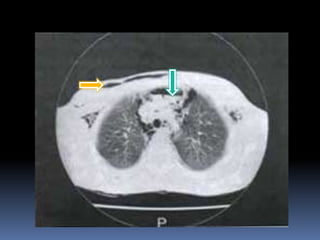

Ruptura Traumática del Diafragma

 Mas común en el lado izquierdo

 Trauma cerrado :

 lesiones radiales que posteriormente se

hernian.

 Trauma penetrante

 pequeñas perforaciones que toman tiempo en

herniarse

 Error dx al inicio por:

 Diafragma izquierdo elevado

 Dilatación gástrica aguda

 Hemoneumotórax lobulado

 Si la sospecha es alta :

 insertar SNG

 Si aparece en el HTI estudios con contrate

 Aparición de lavado peritoneal por el tubo torácico

Dx.